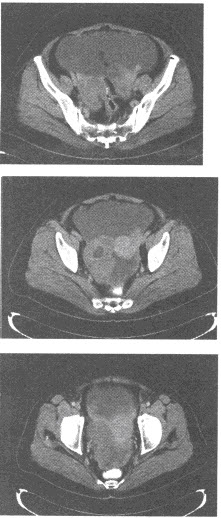

女,53岁,盆腔肿块,伴消瘦乏力,根据所提供的CT图像:

第1题,共2个问题

(单选题)具有确诊意义的检查是()

A:B超检查

B:MRI检查

C:腹水中找到瘤细胞

D:红细胞沉降率明显增高

E:以上均不是

第2题,共2个问题

(单选题)最可能的诊断是()

A:卵巢囊肿

B:卵巢畸胎瘤

C:卵巢浆液性囊腺癌

D:子宫肌瘤

E:卵巢浆液性囊腺瘤